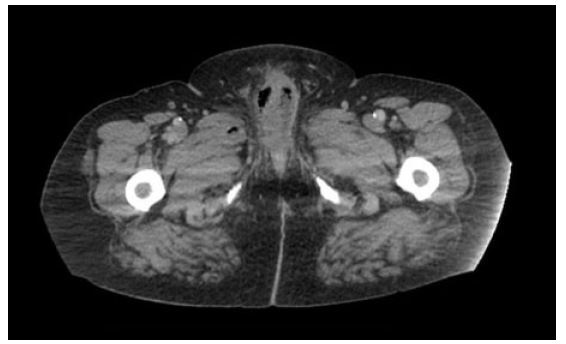

The patient was a 62-year-old male with a history of prostate cancer (s/p RALP with adjuvant X-ray therapy in 2018) and radiation cystitis who presented to the emergency room for three weeks of perineal pain. He did not have a history of diabetes. He reported warmth, redness, and tenderness in the perineum. He also reported that his phallus had been rigid for the past three days. On physical exam there was warmth, erythema, and induration involving the mons pubis, phallus, and scrotum. The phallus was rigid, and the penile glans was pail and dusky. His presenting labs showed a white blood cell (WBC) count of 29.0 and hyponatremia with a sodium of 122. He underwent a computed tomography (CT) scan that showed, “circumferential wall thickening and mucosal hyperenhancement of the urinary bladder, along with several small locules of nondependent gas. There is edema and extensive gas within the penile soft tissues and musculature...” (Figure 1 and Figure 2). He underwent immediate excisional debridement of Fournier’s gangrene.

Figure 1: Initial CT abdomen/pelvis that showed evidence of gas in the penile shaft.

Figure 2: Initial CT abdomen/pelvis that showed evidence of gas in the scrotum concerning for Fournier’s gangrene.